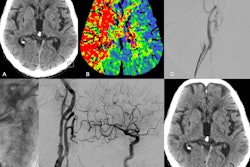

For the case studies, while the researchers noted that HPE may affect any part or system of the body and in rare cases may result in multisystem involvement, the analysis showed that HPE was primarily documented in the brain, the skin and extremities, and the heart; it was also documented in the lungs and kidneys with less frequency.

While the effects and symptoms varied by the organ or systems affected, the authors noted that “Polymer deposits, whether located at the access site or embolized to distant or end organs, have been observed to cause vaso-occlusion, leading to peri- and/or intravascular inflammation, fibrosis, and/or thrombosis.” They also note that the early stages of HPE tend to be asymptomatic; when symptoms manifest, they vary by organ, and some may be nonspecific. Furthermore, they may occur months or even years after the endovascular procedure.